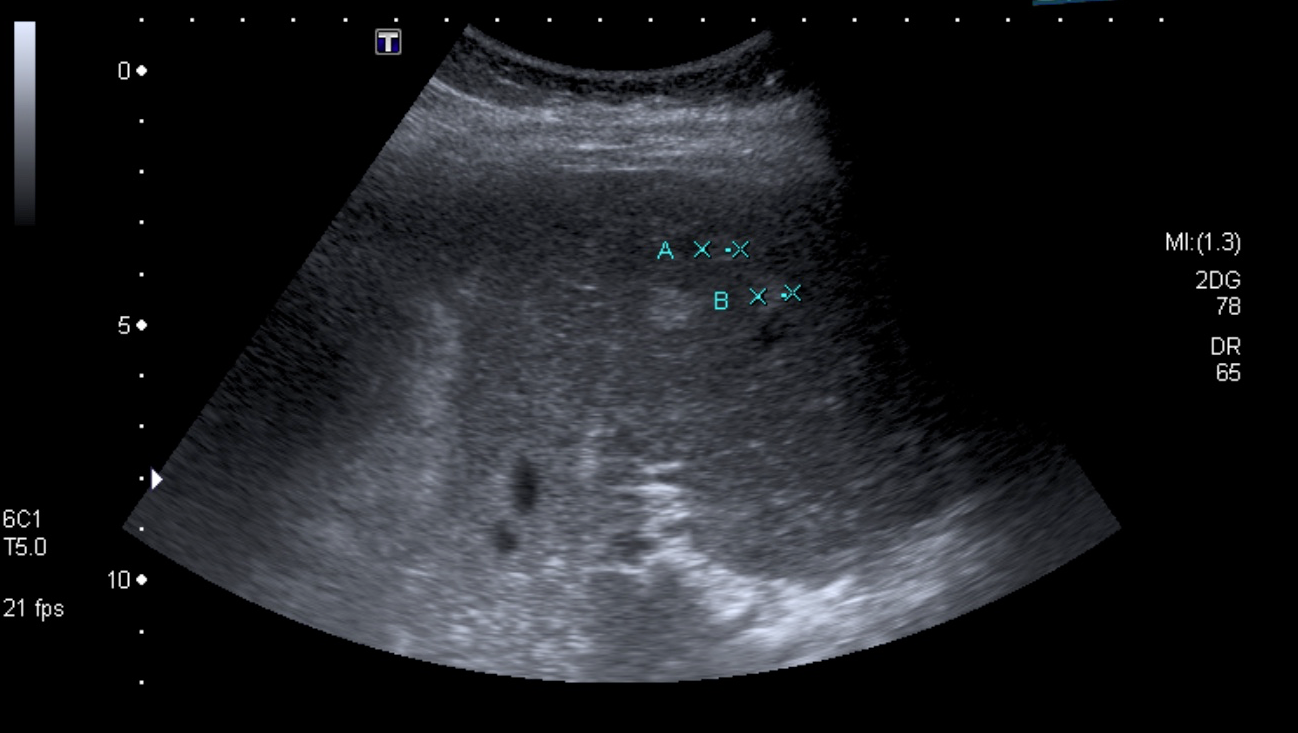

Dolor en hipocondrio derecho

Femenina de 31 años